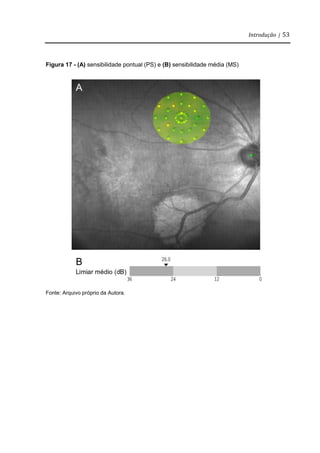

Clinicamente, a interpretação do resultado do exame mostra a sensibilidade

retiniana medida em cada ponto de teste - sensibilidade pontual (PS) (Figura 17A) e

a sensibilidade média (MS) (Figura 17B) em todos os pontos de teste. A análise

Figura 17 - (A) sensibilidade pontual (PS) e (B) sensibilidade média (MS)

Fonte: Arquivo próprio da Autora.